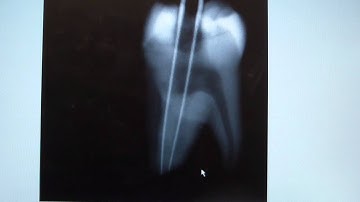

How to take a Distal Shift Shot - SLOB rule